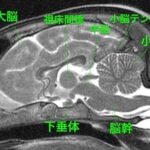

<症例情報> ノルウェージャン・フォレスト・キャット4歳 去勢済みの男の子 主訴:先月初めててんかん発作を起こし、来院日も2回発作。 &nb…